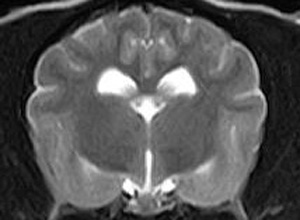

けいれん発作が出るワンちゃんが来院されました。MRI検査では脳に構造上の異常を認めず、脳脊髄液検査でも異常を認めず、特発性てんかんとの診断でお薬での治療となりました。発作は現在のところ、お薬で良好にコントロールされています。